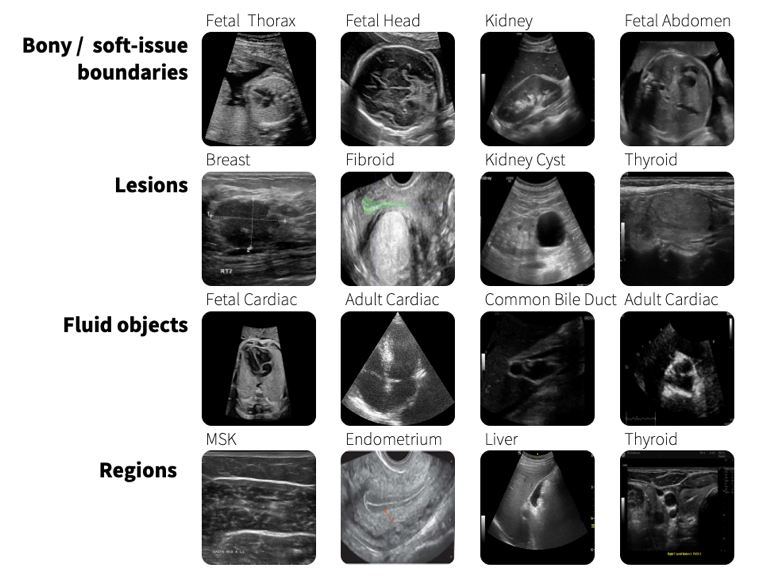

Foundation models can help mitigate the challenges presented by the need for constant customization of AI models. These models can be trained on a broad range of multimodal data enabling them to be applied across different healthcare tasks without extensive retraining. GE HealthCare has been pioneering the development of purpose-built foundation models in healthcare. To give one example, SonoSAMTrack 1 is a foundation model in the research stage that offers a tool for interactive segmentation of objects of interest on ultrasound images and scans. It is designed to adapt to new data and tasks without requiring extensive retraining.